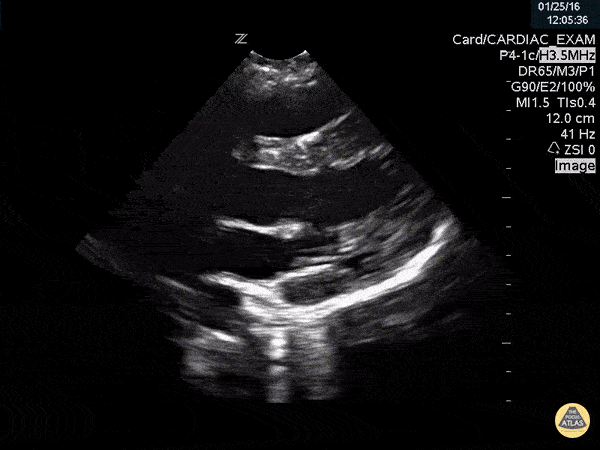

Type A Aortic Dissection on US

| 01:31, 25 October 2017 | 600 × 450 (1.18 MB) | Bobzmac (talk | contribs) | Type A Aortic Dissection on US |